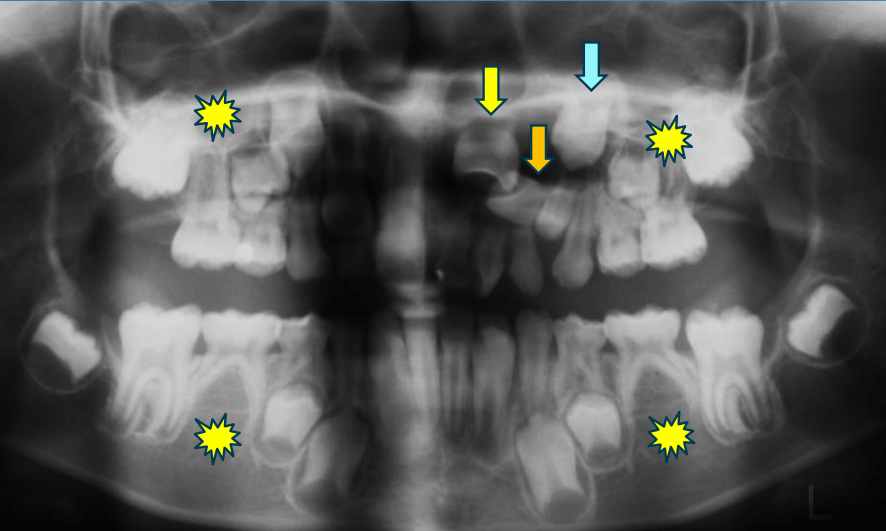

| 年齢・性別 | 8歳3ヶ月の男児 |

|---|---|

| 主訴 | 上顎前歯の位置異常に不安を抱え、歯並びと将来的な咬合状態を整える目的で来院された患者様です。 特に左側の前歯(中切歯および側切歯)の萌出が確認できないことがきっかけとなりました。 |

| 治療期間・回数 | 約5年10ヶ月 |

| 費用 | 460,000円(税別) |